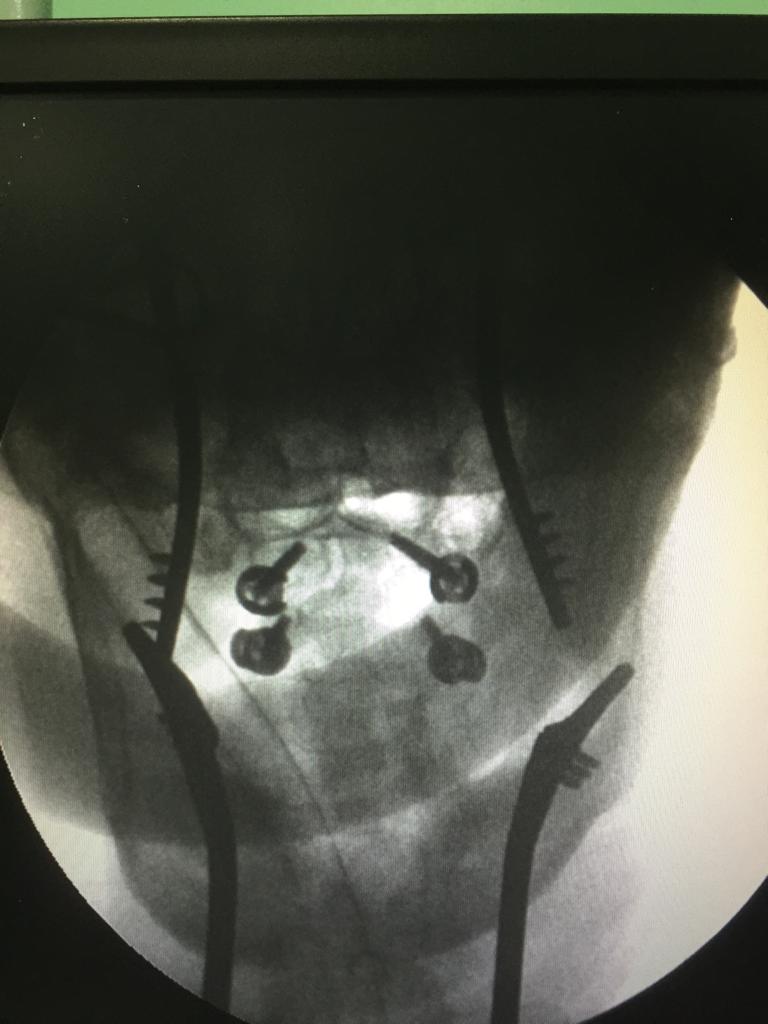

Cases